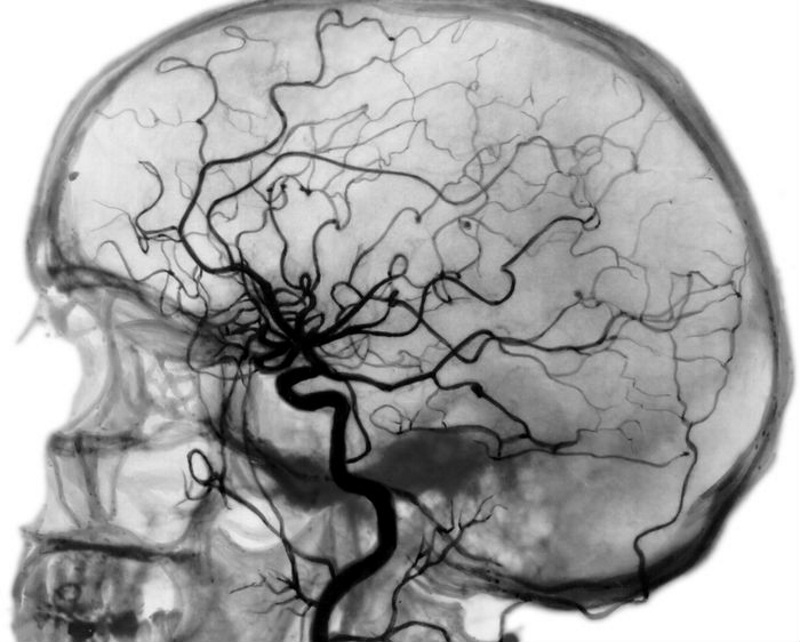

В настоящее время цереброваскулярные поражения, такие как атеросклероз, тромбозные окклюзии и стенозы являются одними из основных жизнеугрожающих состояний. Наиболее частым последствием стеноза артерий головного мозга является ишемический инсульт с последующим инфарктом мозговой ткани. Компьютерная томография в диагностике данной патологии получила наибольшее распространение среди остальных средств нейровизуализации. Однако обычная КТ не позволяла оценить перфузию ткани мозга и определить причину инфаркта. Поэтому её стали проводить с внутривенным введением контрастного вещества и метод стал называться КТ-ангиографией. Доступность исследования позволяет полностью отказаться от традиционной рентгеновской ангиографии и имеет ряд преимуществ перед МР-ангиографией.

Преимущества КТ-ангиографии сосудов головного мозга

- доступность (в сравнении с МРТ);

- высокая разрешающая способность;

- возможность исследования тонких срезов в любой проекции (при МСКТ);

- изучение интересующей области в трехмерном виде;

- визуализация не только просвета сосуда, но и его стенки;

- меньшая лучевая нагрузка в сравнении с классической рентгеновской ангиографией.

В отличии от МР-ангиографии, во время которой обнаруженная атеросклеротическая бляшка проявляется потерей МР-сигнала, а, следовательно, невозможно исследовать состояние васкулярной стенки, по данным КТ-ангиографии можно выявить минимальный размер просвета стенозированного сосуда и даже характер бляшки- фиброзный, кальцинированный или же смешанный.

Также, в отличие от МР-ангиографии КТ-ангиография позволяет сканировать металлические стенты и не дает артефактов от измененного (например, турбулентного) кровотока, где на МР-ангиограммах сигнал практически отсутствует.

- проводится реконструкция полученных изображений в проекции максимальной интенсивности (MIP) в трех плоскостях для исследования сосудов, в проекции мультипланарной реконструкции (MPR) для обнаружения атеросклеротических бляшек и участков вазоспазма, также проводится 3D-реконструкция сосудов Виллизиевого круга.

КТ ангиография позволяет комплексно обследовать артерии и вены головного мозга с использованием рентгеновских лучей. Благодаря этому методу диагностики стало реально определить заболевания кровеносных сосудов, а так же проверить их функциональность и морфологию.

На сегодняшний день все диагностические центры используют современные томографы, которые дают возможность сделать пошаговые снимки-срезы артерий и вен, а так же отобразить их трехмерную модель.